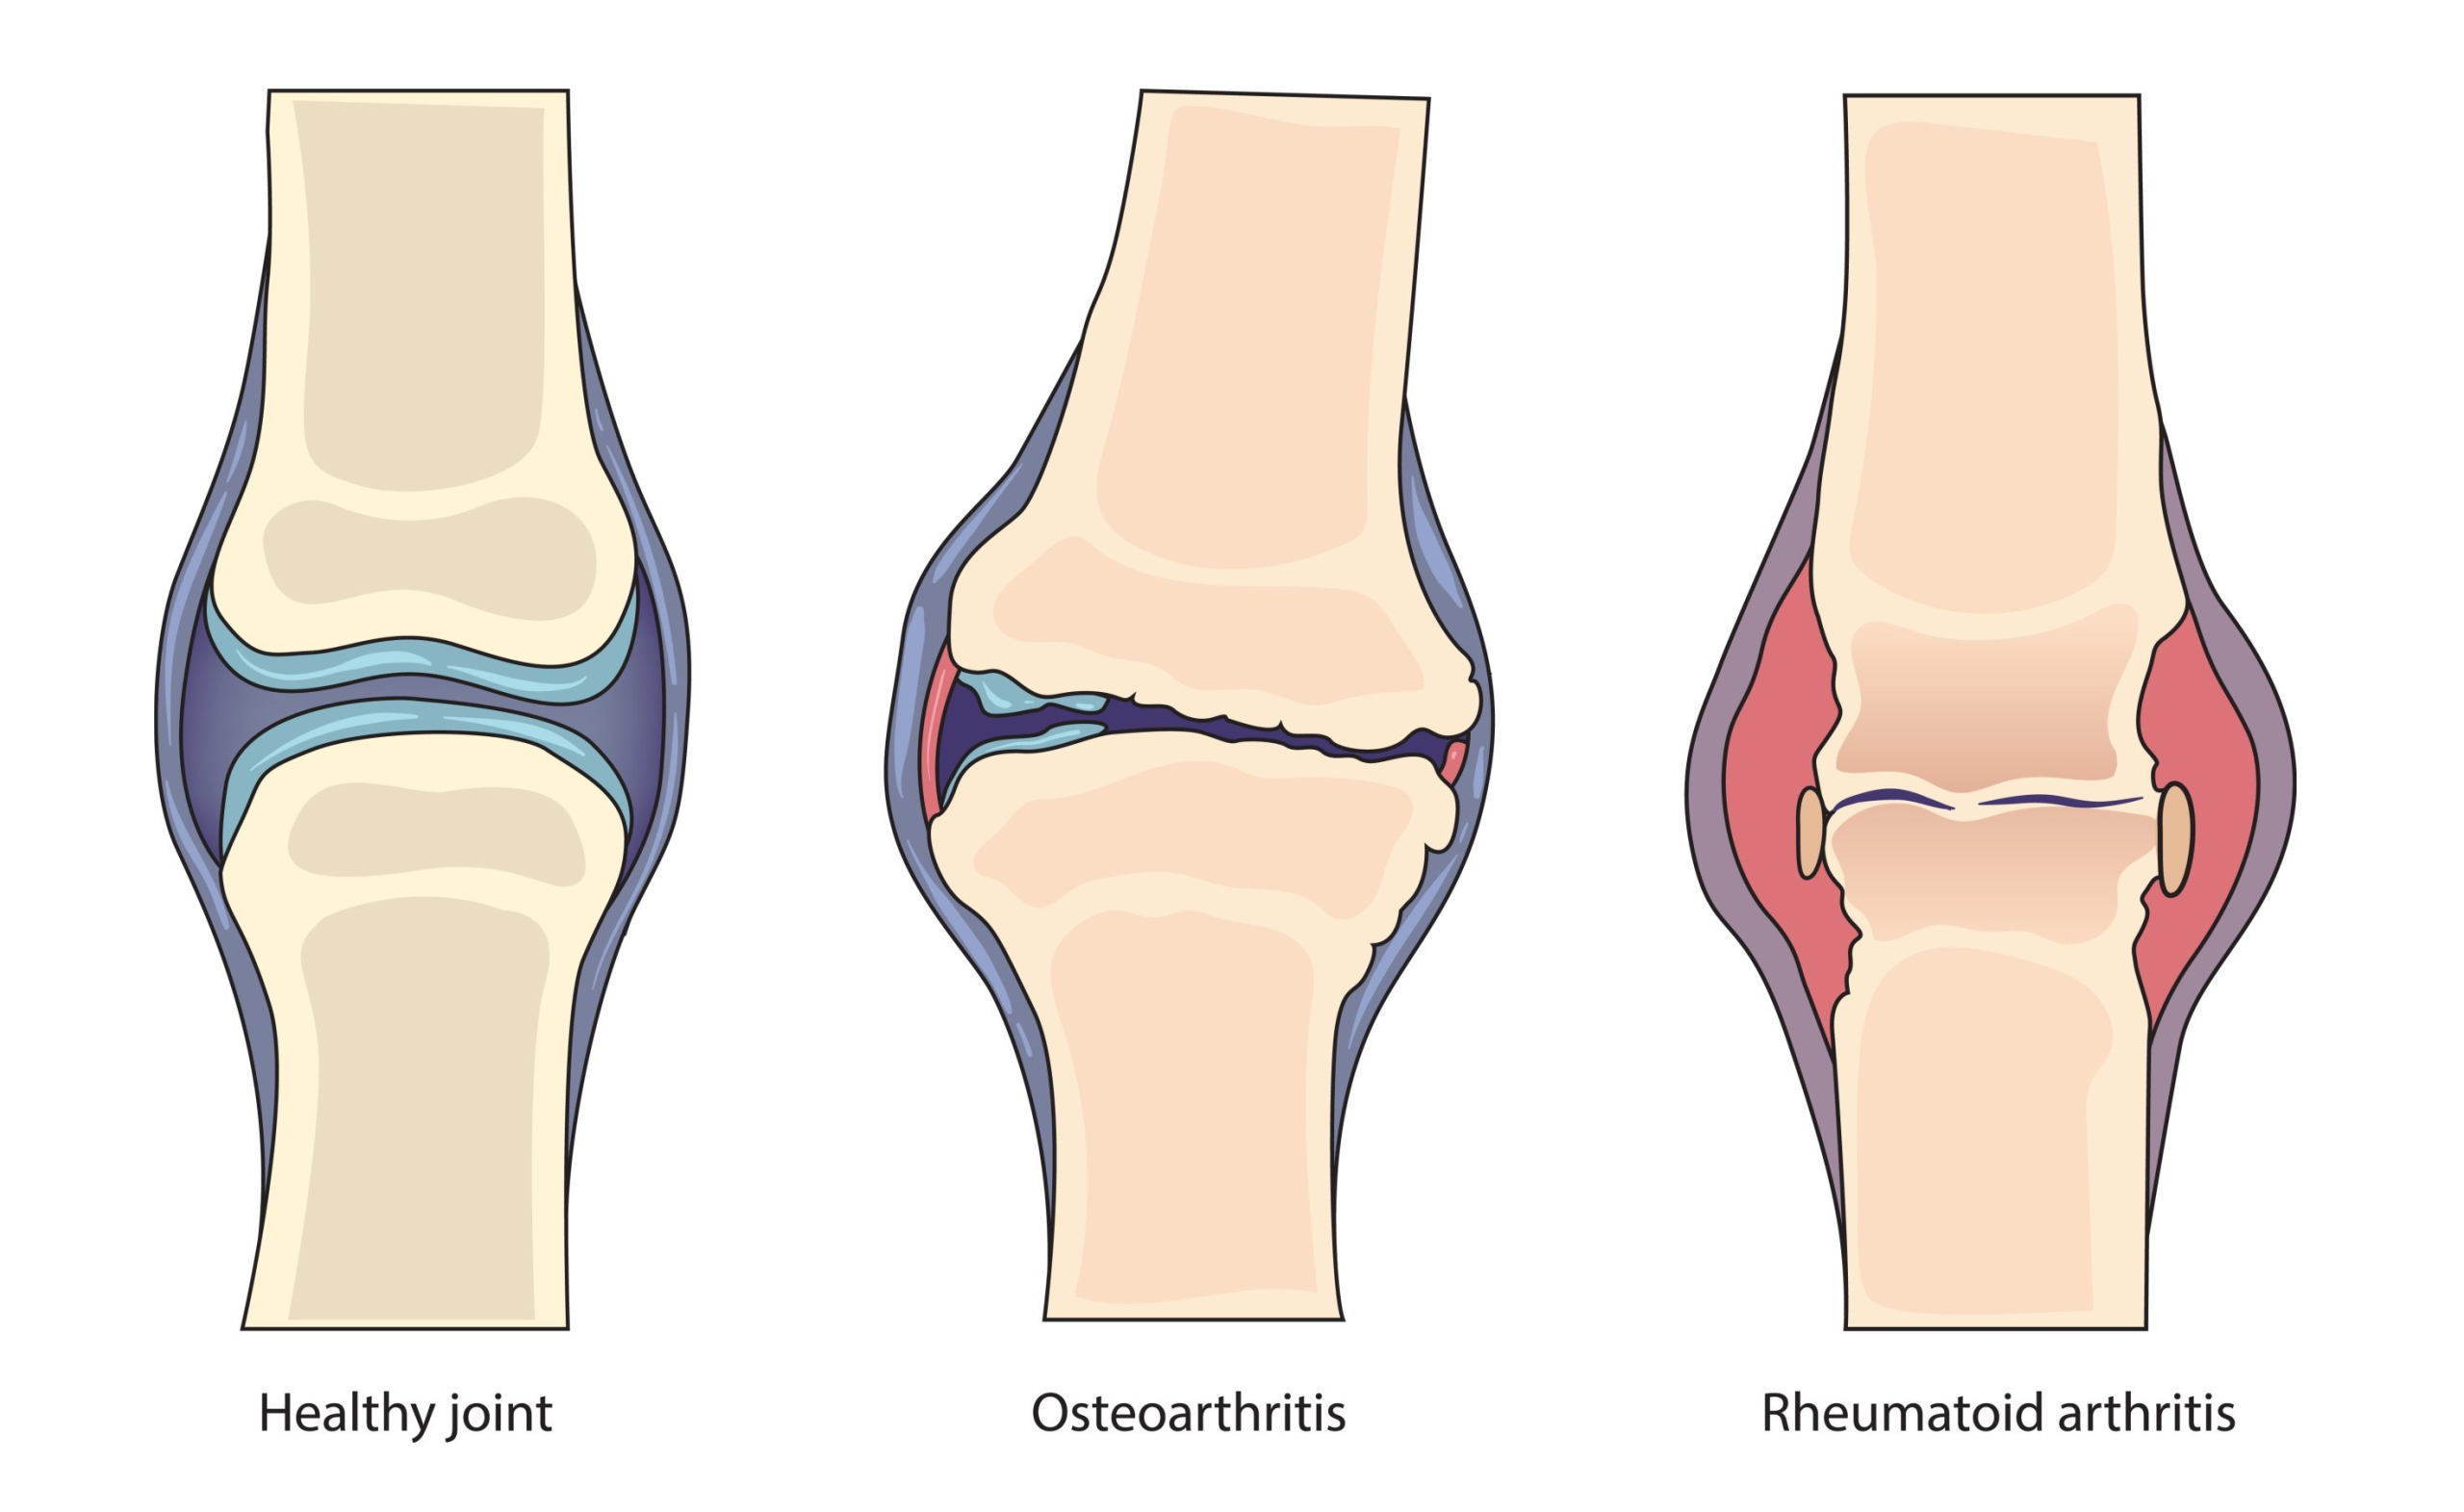

اگرچه آرتروز و آرتریت دو بیماری مرتبط با مفاصل هستند ولی در پاسخ به سوال فرق آرتروز و آرتریت چیست؟ باید گفت که در واقعیت این ها دو تا بیماری متفاوت هستند. که در ادامه توضیح می دهیم.

فرق آرتروز و آرتریت چیست؟

آرتریت یک اصطلاح کلی برای بیماری های التهابی مفصل است و بیش از صد نوع مختلف را در بر می گیرد. این گروه از بیماری ها می توانند علل متفاوتی مانند اختلالات خودایمنی، عفونت ها یا مشکلات متابولیک داشته باشند و معمولاً با علائمی مثل درد، تورم، گرمی، قرمزی مفصل و خشکی طولانی مدت صبحگاهی همراه هستند. آرتریت میتواند چندین مفصل را به طور همزمان درگیر کند و در هر سنی دیده شود.

در مقابل، آرتروز یا استئوآرتریت شایع ترین نوع آرتریت و یک بیماری غیر التهابی و سایشی مفصل محسوب می شود. در این بیماری، غضروف مفصل به تدریج تخریب می شود که نتیجه آن کاهش حرکت مفصل، درد و گاهی تغییر شکل مفصل است. آرتروز بیشتر در سنین بالا بروز می کند و مفاصلی مانند زانو، لگن، ستون فقرات و انگشتان را درگیر می سازد.

درد در آرتروز معمولاً با فعالیت تشدید شده و با استراحت کاهش می یابد و خشکی صبحگاهی آن کوتاه مدت است. برخلاف بیشتر انواع آرتریت، در آرتروز علائم واضح التهاب مانند قرمزی و گرمی شدید کمتر دیده می شود و مدیریت بیماری بیشتر بر اصلاح سبک زندگی، تقویت عضلات، کاهش وزن و کنترل درد تمرکز دارد.